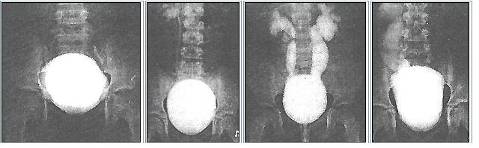

Рентгенограма хворих з СМР

При 1‑й степені закид контрасту з сечового міхура походить тільки в нерозширений сечовід.

При 2‑й степені заповнюють нерозширений сечовід і нерозширений чашечко-мискова система (ЧМС) нирок.

При 4‑й степені і вони стають заокругленими.

При 5‑й степені характеризується масивною делятацією і звивістю верхніх сечових шляхів.